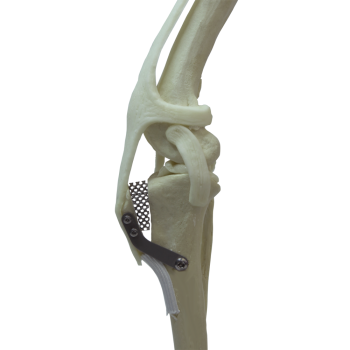

Avanzamento della tuberosità tibiale (TTA)

La TTA porosa (Tibial Tuberosity Advancement Porous) è una tecnica chirurgica utilizzata per il trattamento della rottura del legamento crociato craniale nel cane.

Si tratta di un’evoluzione della tecnica TTA tradizionale, che prevede l’utilizzo di impianti in titanio poroso: questo materiale favorisce una migliore integrazione ossea e una guarigione più stabile e rapida.

La TTA non “sostituisce” il legamento crociato, ma riconfigura la biomeccanica: avanzando la tuberosità tibiale, l’angolo del tendine del quadricipite/patellare rispetto al plateau tibiale (Patellar Tendon Angle, PTA) viene portato attorno a 90° in carico, riducendo la componente di taglio craniale e stabilizzando dinamicamente l’articolazione.